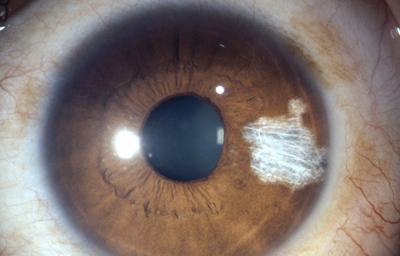

En la cara Anterior esta el pigmento que le da el color al Iris y dependiendo del grado de reabsorción u atrofia de esa capa anterior se pueden observar:

Las Criptas de Fuchs: que son pequeñas aberturas alrededor del collarete, producto de la atrofia o reabsorción de la hoja anterior del iris, que le permiten al estroma y a los tejidos mas profundos estar en contacto con el humor acuoso.

Cuando el Iris no tiene criptas, se considera que la reabsorción u atrofia de la hoja anterior (memb. pupilar) se detuvo en el circulo menor.